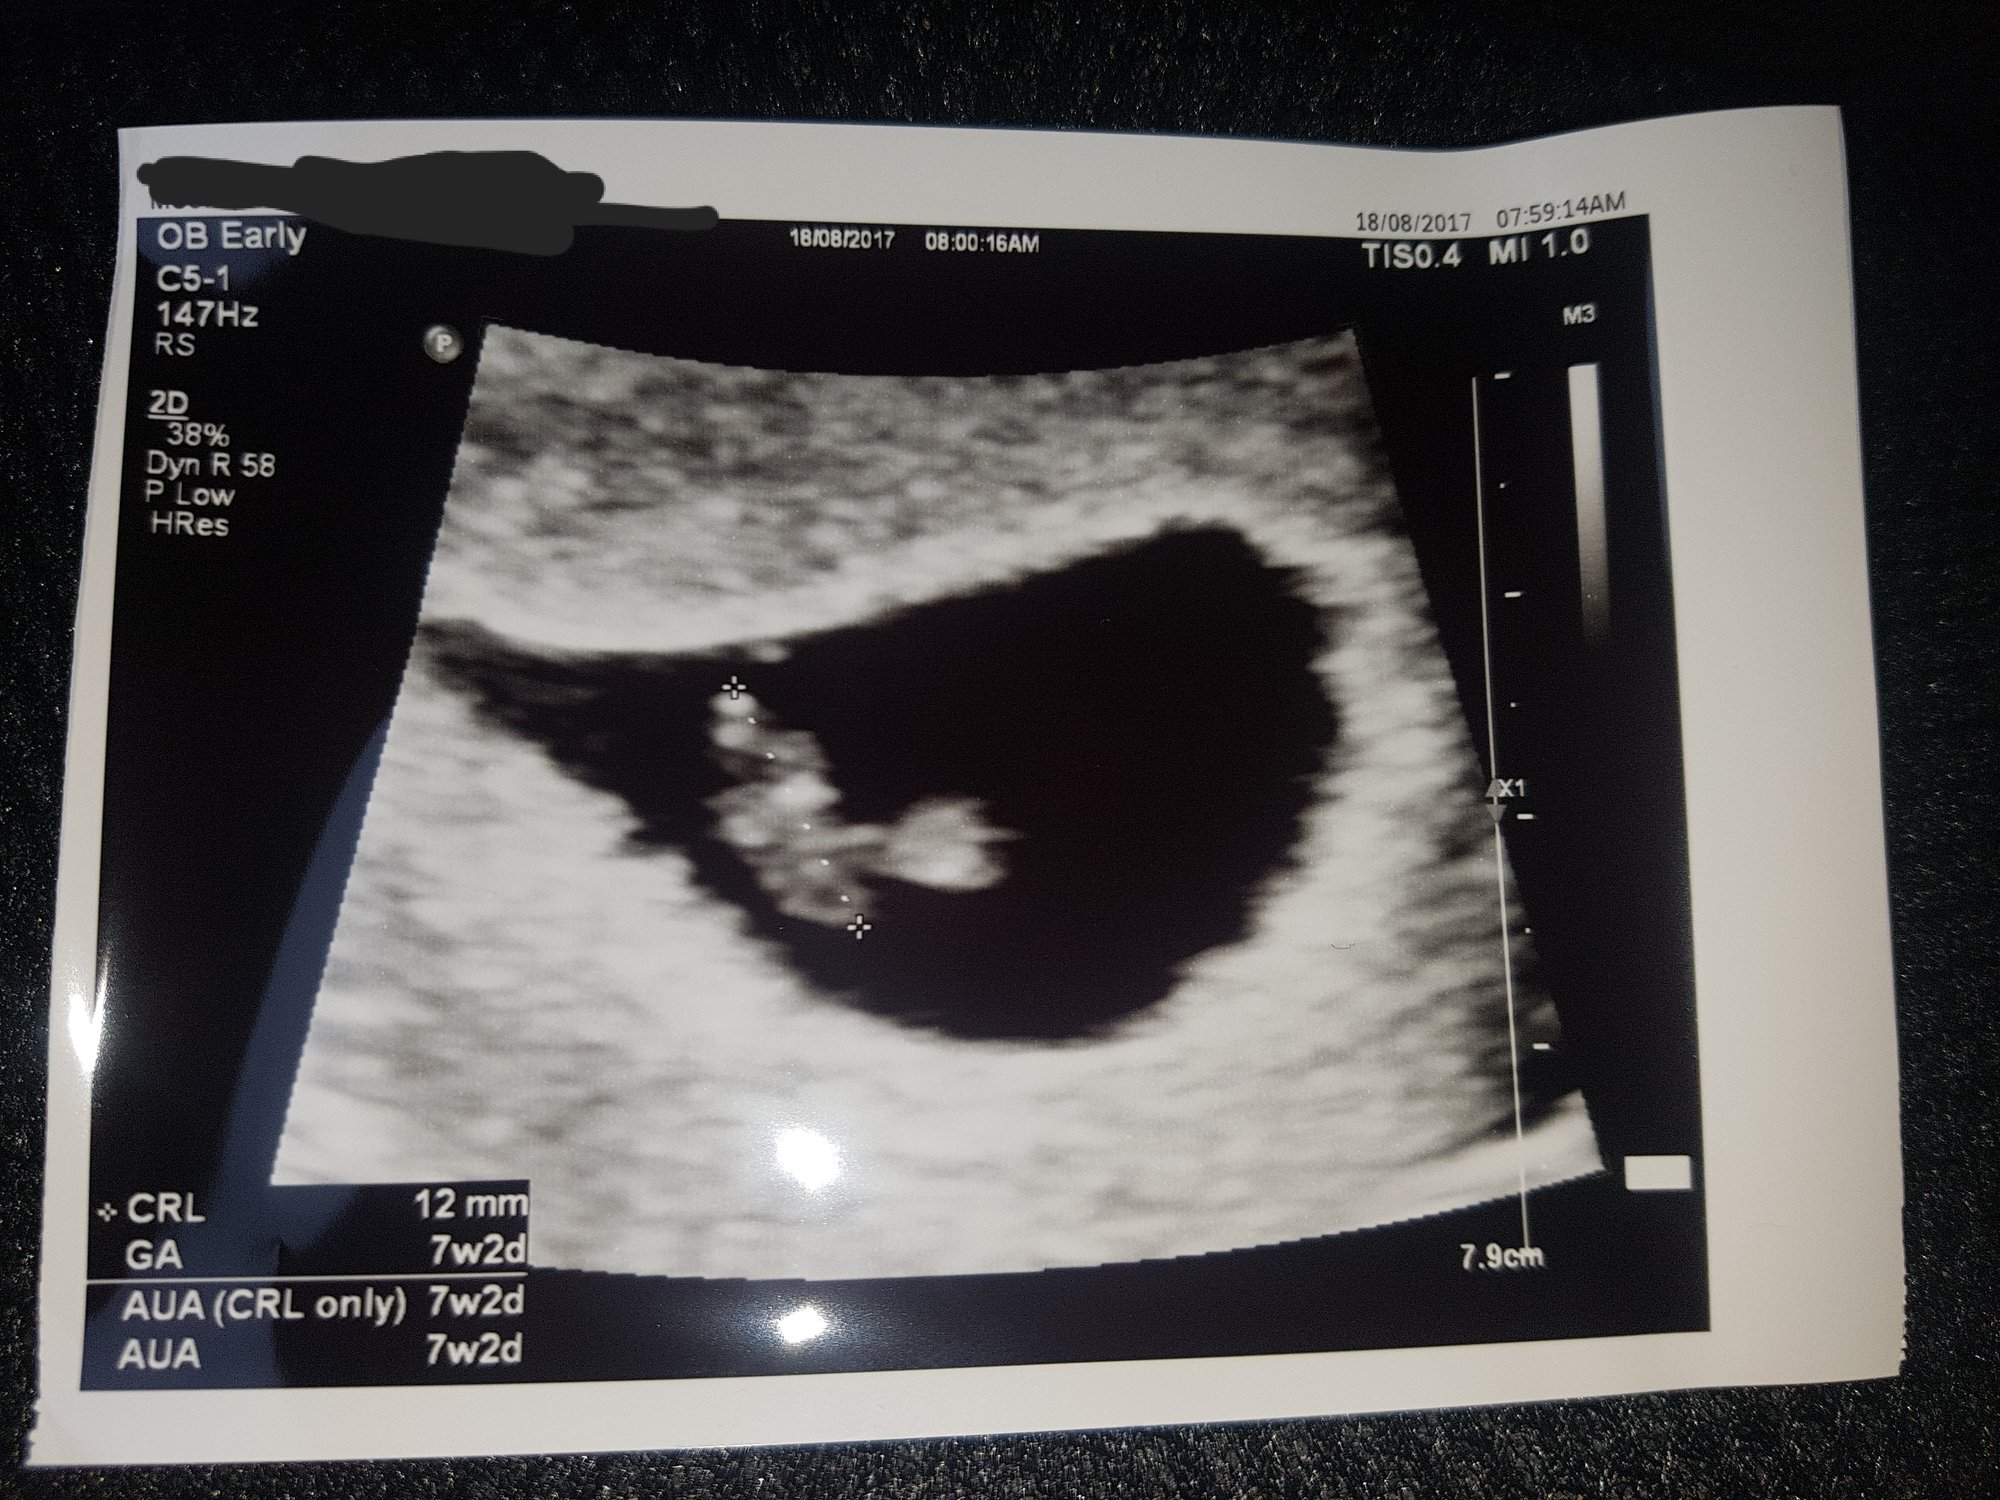

Here's my picture from this morning! Baby is right on track at 7 wks 2 days and I got to hear the heartbeat! It was 157 bpm. I go back August 30th for another ultrasound, it should be the last one with my RE.

I had my dating scan a few days ago, they adjusted my due date, bringing it 3 days earlier to 1 April 18. Making me 7wks2d at the date of the scan All normal and excited now ive actually seen my peanut.